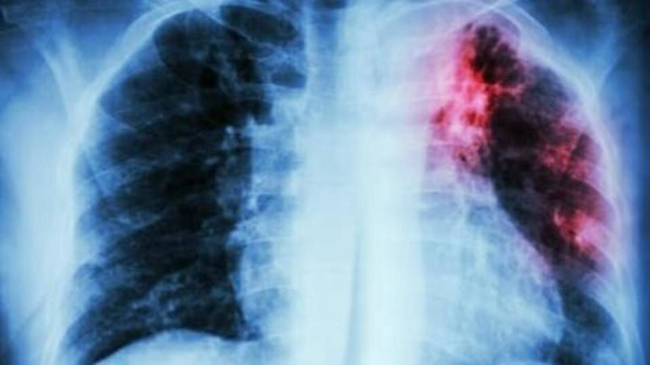

Тирасполь, 18 октября. /Новости Приднестровья/. В 2021 году в Приднестровье было зафиксировано 53,3 случая туберкулёза на 100 тысяч населения. При этом количество заболевших уменьшается на 5-8% в год. Об этом сообщила газета «Приднестровье», сославшись на главного врача Республиканской туберкулёзной больницы Сергея Осадчего.

Положительную роль сыграл масочный режим, введённый в период пандемии. Люди меньше контактировали друг с другом. Вместе с тем уменьшился и охват населения флюорографией, которая является главным методом профилактического обследования. Как следствие, если в 2019 году заболевание на ранних стадиях выявлялось у 15%, то в 2021-м – только у 5%.

Соответственно, увеличилось число поздних тяжёлых форм туберкулёза, которые сопровождаются распадом лёгочной ткани, бактериовыделением. Пациенты обращаются к врачу уже по факту, по клиническим проявлениям. Оставаясь долгое время дома, не проходя флюорообследование, больные заражают детей, отсюда и небольшой рост детского туберкулёза.